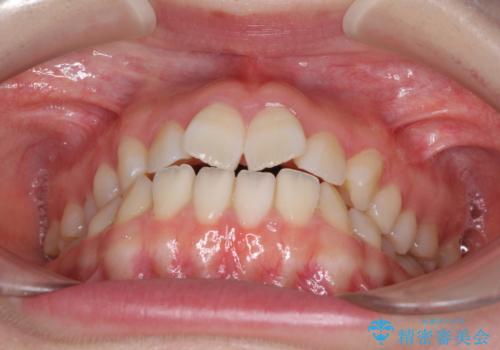

- 前歯の捻れと、ちょっとした出っ張りを気にして来院された患者様です。

歯と歯の間を削る(IPR)ことでデコボコを解消し、インビザラインで整えることとしました。

インビザライン治療特有の奥歯が接触しない時期が続き、当初予定よりも期間がかかりましたが、最終的には安定した咬み合わせと、整った前歯になりました。